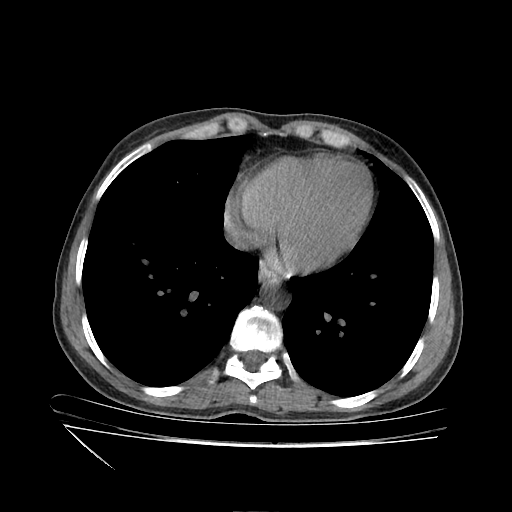

Generated VENOUS CT scan (A→B translation)

No window - Raw intensity values

Lung window (WL -600, WW 1500 β†’ Low βˆ’1350, High +150)

Mediastinum window (WL 40, WW 400 β†’ Low βˆ’160, High +240)